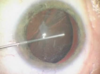

Qual a tríade clássica da síndrome da íris flácida intraoperatória?

1 - Abaulamento e flacidez da íris

2 - Prolapso da íris pela incisões

3 - Miose progressiva